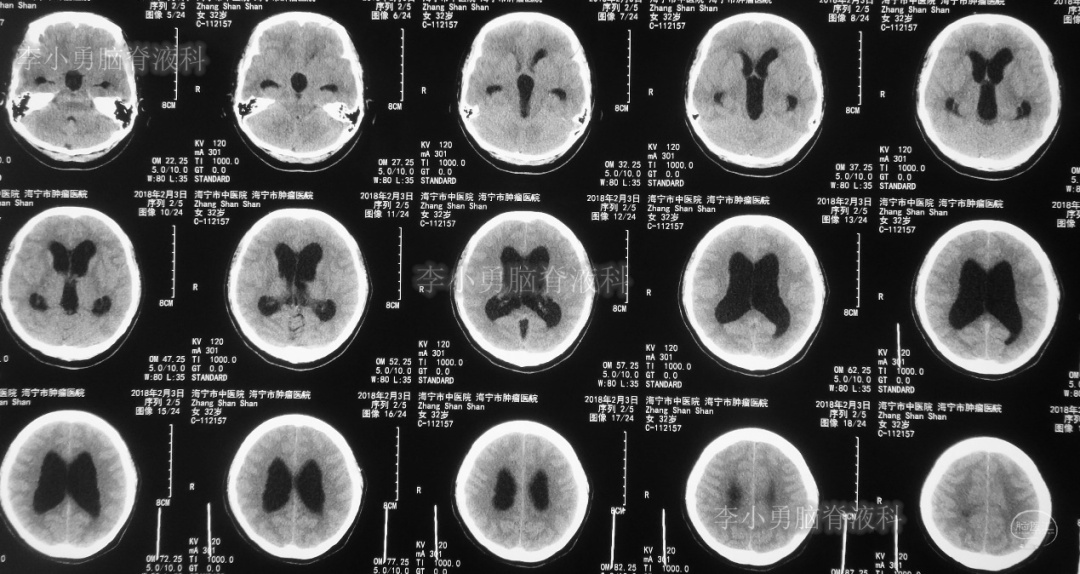

患者于2018年1月29日,突发头痛、头晕、恶心、呕吐,并高热40度。在当地医院门诊输入4天抗生素后发热缓解,但出现了双眼不能上视(眼球不能向上看)。5天后即2018年2月3日,在当地的第1家医院:浙江省海宁市某医院行头颅CT(图-1)发现脑室扩张,当地医院诊断为“梗阻性脑积水”。

图-1:2018年2月3日头颅CT